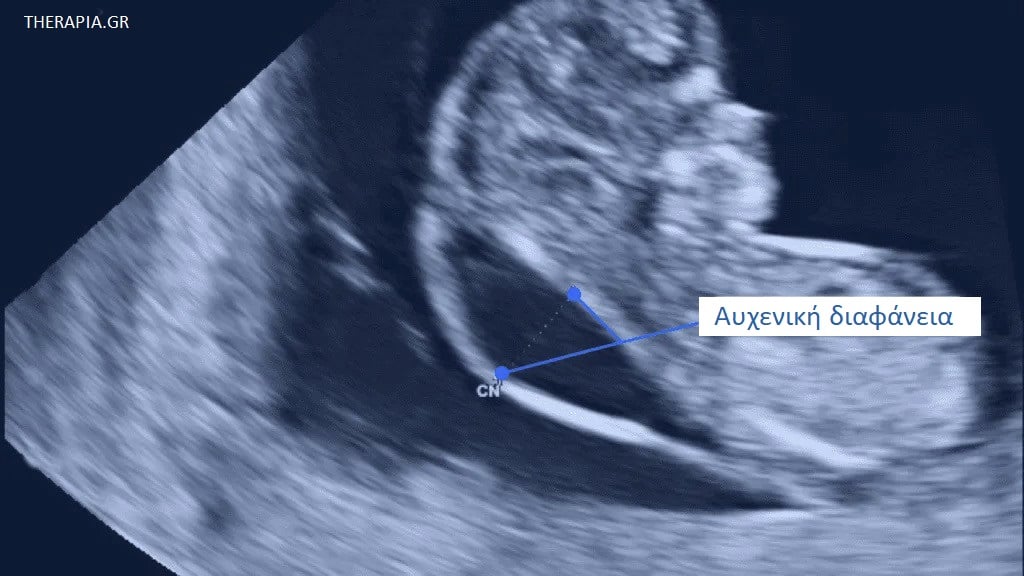

Αυχενική διαφάνεια

Η αυχενική διαφάνεια είναι μια υπερηχογραφική εξέταση που μετρά το πάχος του χώρου πίσω από τον λαιμό του μωρού σας (11η-14η εβδομάδα της κύησης).

Κάθε αγέννητο μωρό έχει κάποιο υγρό κάτω από το δέρμα στο πίσω μέρος του λαιμού του. Αυτό το υγρό ονομάζεται αυχενική διαφάνεια (ΑΔ).

Μπορείτε να δείτε αυτό το υγρό στο υπερηχογράφημα νωρίς στην εγκυμοσύνη σας. Είναι μέρος της φυσιολογικής ανάπτυξης ενός μωρού στη μήτρα, αλλά, εάν το μωρό σας έχει περισσότερο υγρό από το συνηθισμένο, μπορεί μερικές φορές να είναι σημάδι ότι έχει κάποιο πρόβλημα υγείας. Αυτό μπορεί να είναι ένα σωματικό πρόβλημα (για παράδειγμα, ένα καρδιακό πρόβλημα) ή μια χρωμοσωμική πάθηση (για παράδειγμα, σύνδρομο Down).

Τι είναι μια φυσιολογική μέτρηση αυχενικής διαφάνειας;

Δεν υπάρχει μια δεδομένη φυσιολογική τιμή, επειδή η αυχενική διαφάνεια συνήθως αυξάνεται αναλογικά με το μωρό. Αυτό σημαίνει ότι η μέτρηση εξαρτάται από τις εβδομάδες κύησης όταν γίνεται το υπερηχογράφημα.

Ωστόσο, γνωρίζουμε ότι εάν στην αρχή της εγκυμοσύνης σας η αυχενική διαφάνεια είναι 3,5 mm ή περισσότερο, υπάρχει μεγαλύτερη πιθανότητα το μωρό σας να έχει κάποιο σωματικό πρόβλημα ή χρωμοσωμική πάθηση.